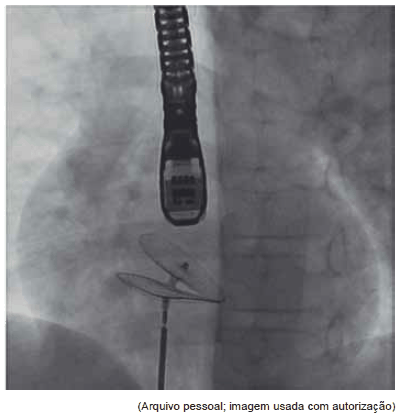

Em consulta médica em UBS, em março do presente ano, mãe refere que seu filho passou mal, com taquicardia e dispneia em jogo de futebol de campo, em 2021. Foi examinado e realizou radiografia de tórax, eletrocardiograma e ecocardiograma. Mãe não trouxe exames. Ao exame físico verificou-se estar em bom estado geral, frequência cardíaca de 71 bpm, frequência respiratória de 16 irpm, pressão arterial sistêmica nos 4 membros de 90 x 60 mmHg e bulhas rítmicas normofonéticas com desdobramento constante de segunda bulha. Foi submetido a tratamento percutâneo.

O diagnóstico da cardiopatia congênita é: